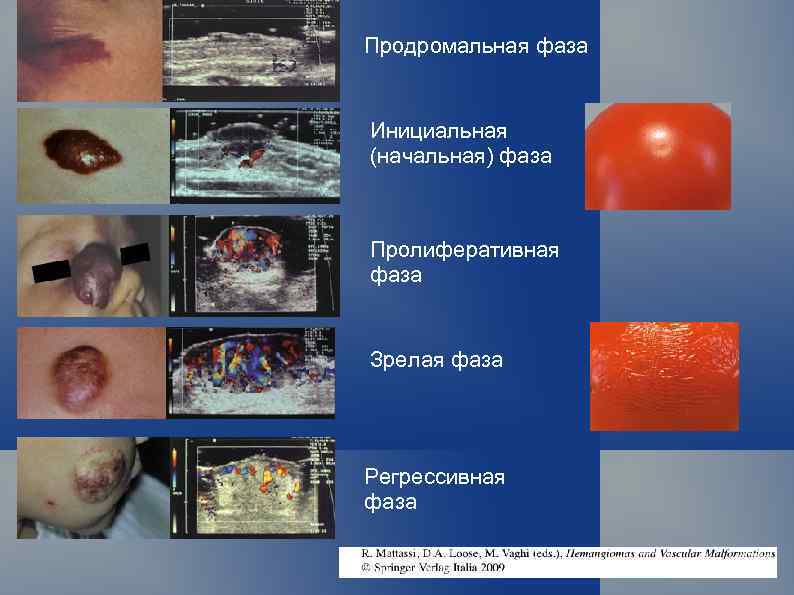

Продромальная фаза Инициальная (начальная) фаза Пролиферативная фаза Зрелая фаза Регрессивная фаза